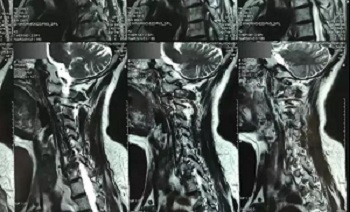

九、翻拍磁共振图像时,因为磁共振片子很大,而且一张片子上有很多图像(如下图),所以,单纯的拍一张片子,因为手机拍摄,像素以及翻拍质量不好,且放大后图像会发虚,细节看不清楚,所以,基本上是没用的,对于医生阅片来说,质量太差,不能获取图片上的有效信息。

十、因此需要将磁共振的一张片子,进行分区域局部放大拍摄,尽可能的将片子上的细节拍摄清楚,将一张磁共振片子进行分区。

十一、将分区的磁共振图像,按顺序进行拍摄,即可获取如下比较有价值的清晰图片